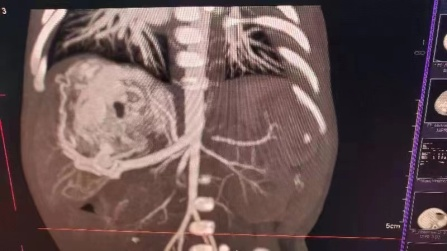

患儿妈妈怀孕期间产检发现肝脏占位,血运丰富,并随着时间的推移,肝脏占位逐渐变大,孕38+5周外院彩超提示肝脏肿块增长至7.3*4.3cm。宝宝出生后第一天即出现拒乳、呼吸困难、心率快等表现,考虑宝宝的情况为肝脏的血管瘤并有肝动-静脉瘘,引起心脏持续高动力状态,导致心功能不全,这是一种能够危急患儿生命的紧急情况,需要及早干预治疗,家属遂即慕名转至我院新生儿科。入住新生儿科后王惠萍教授紧急联系B超室乞艳华副教授完善心脏以及肝脏彩超评估患儿心功能以及瘤体大小,宝宝的肝脏占位正逐渐增大,心功能逐渐恶化,留给家属和医生的时间正在减少;小儿外科高亚教授心系患儿安危,多次查看、询问患儿情况,并根据每次复查指标,作出指示:决定使用微创介入的方式进行肝动脉栓塞术,封堵肿瘤血供。但新生儿血管纤细,动静脉瘘广泛,新生儿设备、管路、用药禁忌等诸多难题,成功的案例国内外鲜有报道,西北地区尚无类似病例报道。为了给患儿争取生存的机会,组织影像科介入组、小儿外科、麻醉手术科、医用超声科、新生儿科等院内多学科MDT团队进行了评估以及手术方案讨论, 反复论证手术的可行性,提出手术可能存在的风险以及应急策略并做好充分准备。

3月13日,在小儿外科高亚教授、郑百俊教授及郭新奎教授及多学科的积极配合下,为患儿进行了肝动脉造影术+肝动脉栓塞术。新生儿股动脉纤细,常规股动脉鞘作为入路存在术后股动脉闭塞下肢缺血风险,采用了经股动脉单纯微导管超选择性栓塞,手术难度大大增加,但避免了股动脉缺血风险。

在麻醉科(吴刚副主任,罗倩倩、陈趟医生)和新生儿科(王惠萍教授、王莉医生)的保驾护航下、超声科(何鑫医生)的精准定位置管,血管介入团队(彭玉萍教授、刘强教授、杨晓东医生)经过3小时的努力,共封堵四处肝血管瘤的主要供血动脉分支,手术过程患儿生命体征稳定,血管瘤的血流量逐渐减少,进行心功能测定显示心输出量较术前下降,效果显著,肝脏的“扫雷”行动获得阶段性的成功,在场的所有医务人员为孩子鼓掌加油!